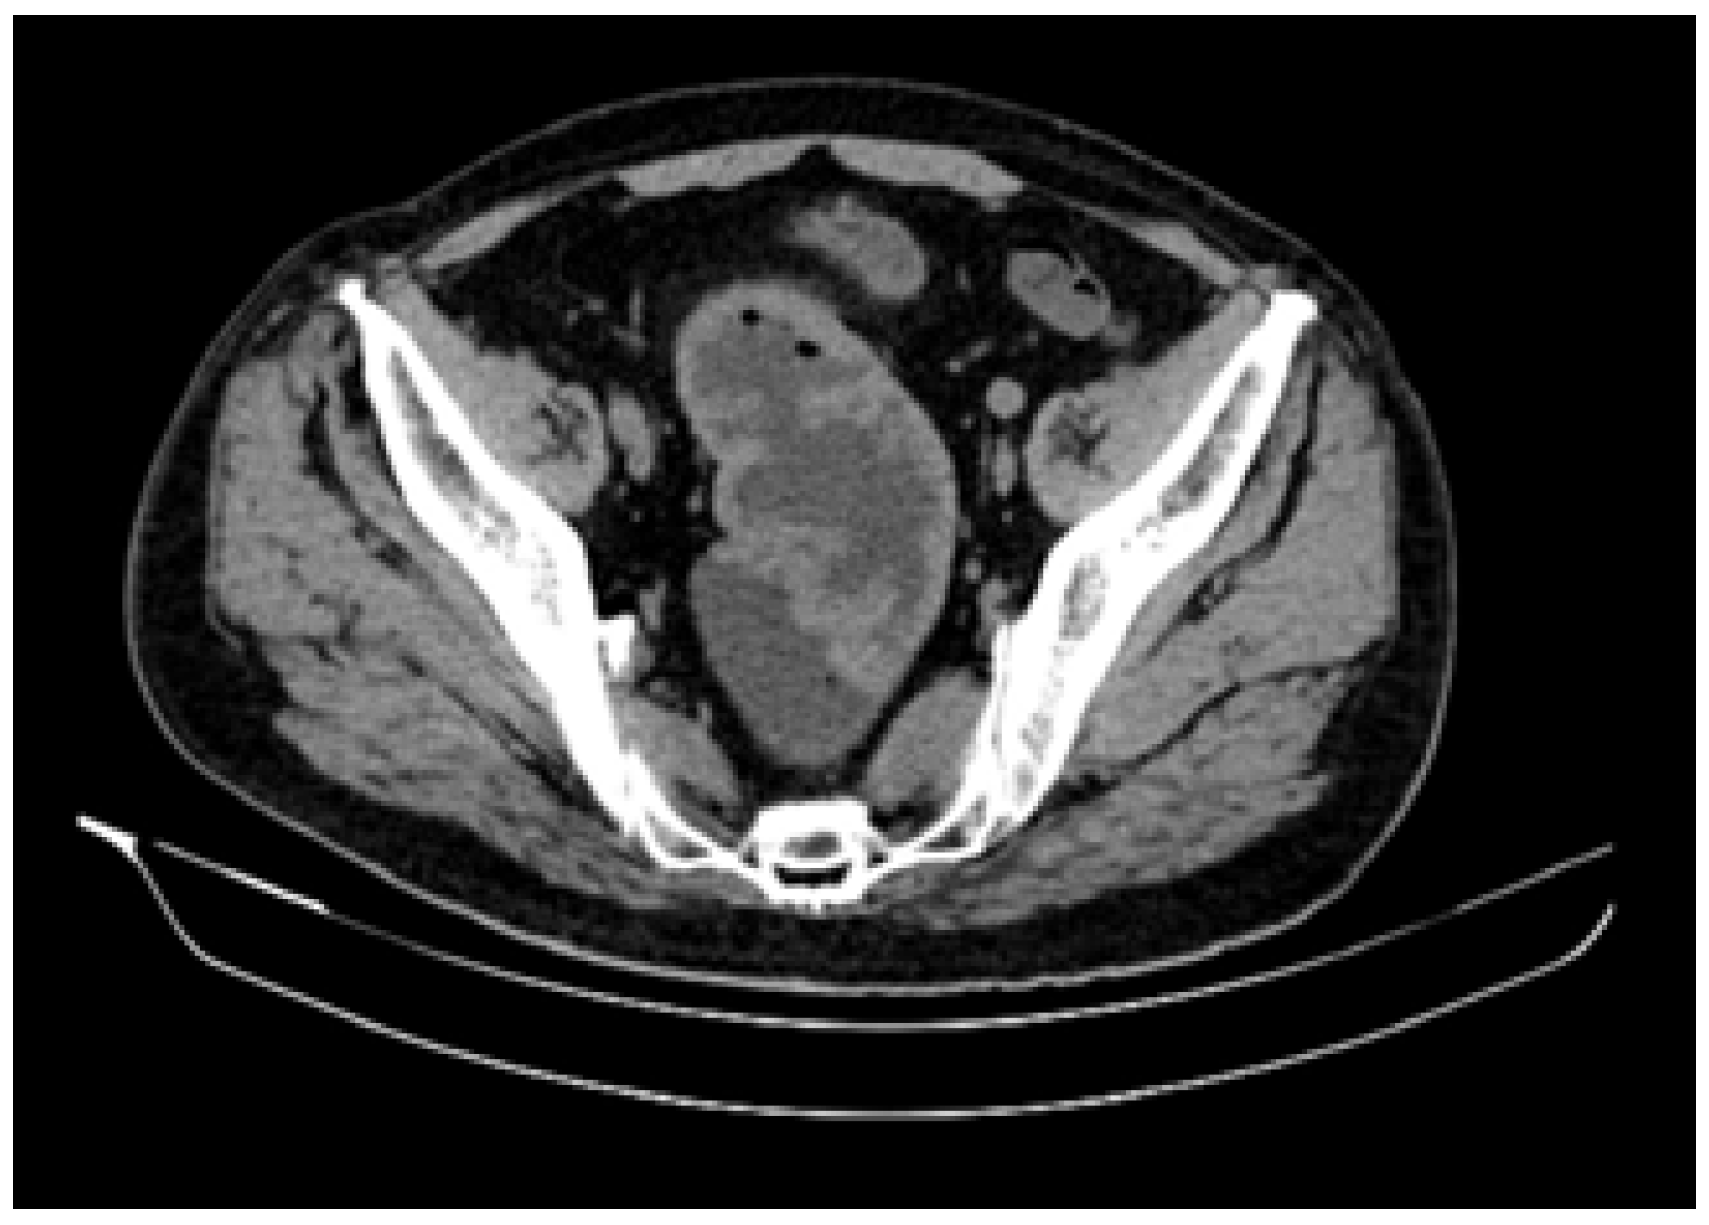

Thoracic, abdominal and pelvic computerized tomography (CT) scan was performed, revealing a large and circumferential mass of 12 cm in length, located 8 cm from the anal verge. The recto-sigmoid wall was 2 cm in thickness, with no evidence of extramural invasion (Figure 3).

Figure 3.

Computer tomography features—a 12 cm in length and 2 cm in thickness recto-sigmoid circumferential tumor.